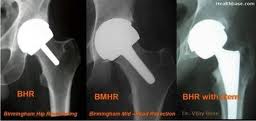

The report by the Institute of Medicine follows several high-profile recalls of medical devices in recent years, like one involving so-called metal-on-metal artificial hips that have failed in thousands of patients, crippling some of them. In its report, the panel found that existing rules used to approve many devices were never intended to play the critical role of screening out dangerous or ineffective products.

The panel urged the Food and Drug Administration to devise a new approval system for so-called moderate risk devices – a category that now includes artificial hips, external heart defibrillators, and hospital pumps – concluding that the current one was not fixable.